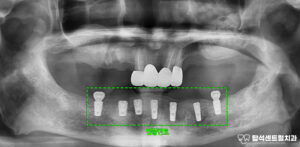

의정부 용현동 치과 : 신경치료가 되어있는 앞니 뿌리 부러짐, 발치 후 임플란트 즉시 식립 & ISQ 측정

안녕하세요. 의정부 용현동 치과 의사 곽승원입니다. ​ 치아의 뿌리가 부러지는 이유로는 스포츠 활동 시 공이나 다른 물체에 맞거나, 넘어지면서 바닥에 얼굴을 부딪히는 경우가 있습니다. ​ 또한 딱딱한 음식을 먹다 갑자기…